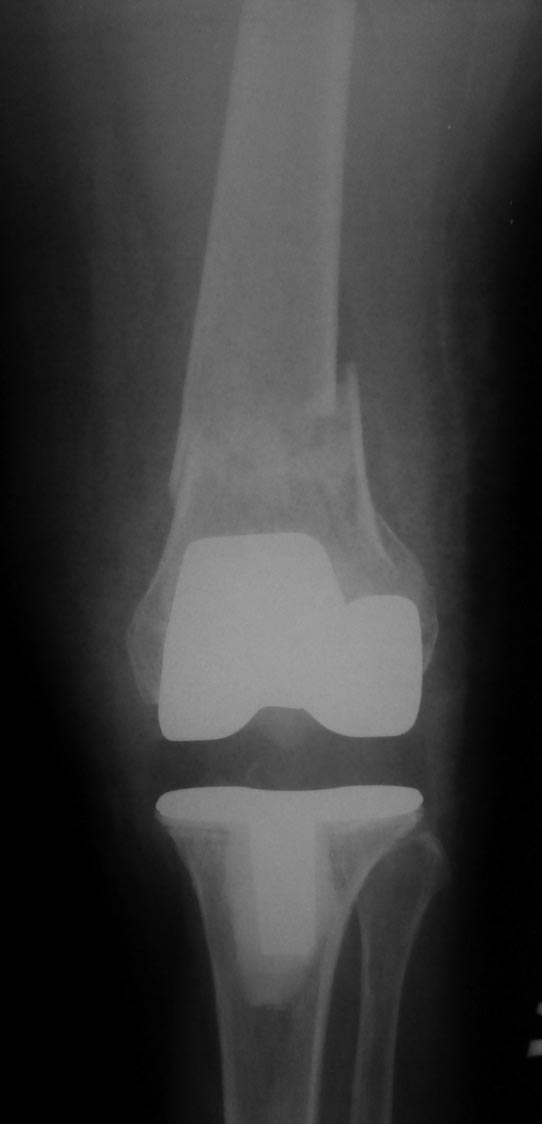

Вот обещанный в чем-то похожий случай. Пациентка 58 лет с тяжелым ревматоидным артритом. Оперировал в 2013 г. В одну сессию сделал чрескожно повторную операцию на стопе (раньше где-то оперировали, пациентка приехала издалека) и малоинвазивный артродез голеностопного сустава (имелась варусная деформация, как компенсация вальгуса колена, на фоне выраженной ревматоидной артропатии). А через неделю – протезирование коленного сустава (фиброзный анкилоз после когда-то выполненной синовэктомии, грубая вальгусная деформация). Понятно, что неделю между операциями стопа торчала в сторону и не была опороспособной. Основное пожелание по коленке было, чтобы сгибалась хоть немного для походов в театр. В конечном счете, сустав сгибался до 90 гр. Фотография стоя была прислана через 2 года после операций. А через 3 года, прошедшим летом, пациентка упала с лестницы: перипротезный перелом бедра. Через 5 дней приехала оперироваться. Отсюда отек на фото стопы. Что интересно, через 2 мес. после остеосинтеза пациентка написала, что только теперь, после перелома, смогла ощутить опору всей поверхностью стопы. До этого пользовалась индивидуальными стельками.